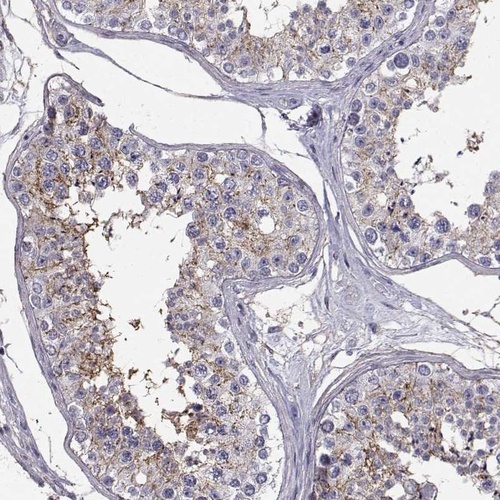

Immunohistochemistry analysis in human testis and endometrium tissues using Anti-SPDYE4 antibody. Corresponding SPDYE4 RNA-seq data are presented for the same tissues.